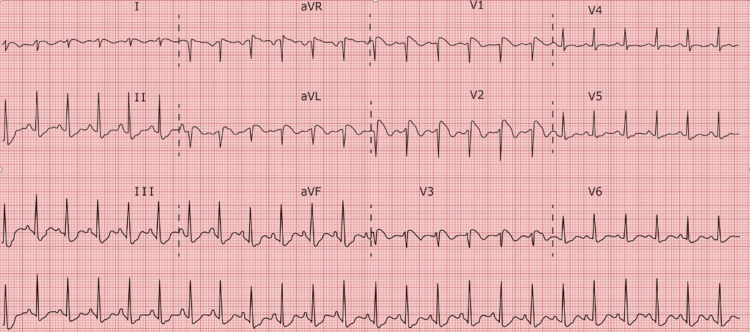

The patient was admitted to the ICU where an arterial line was inserted to enable continuous hemodynamic monitoring, while a neurology consultation prompted the initiation of continuous EEG monitoring to investigate potential subclinical seizures. Throughout the afternoon, the patient displayed persistent tachycardia, leading to the administration of Lopressor to manage heart rate. An ECG was also collected 12 h after the first ECG and was suggestive of a type 1 Brugada pattern (Figure 3).

Also of note is that the patient was severely acidotic on arrival to the ED with an initial venous blood gas pH of 6.694. For those with Brugada syndrome, severe acidosis may cause the sympathetic nervous system to become activated as a compensatory response [ref. 14], intended to stabilize the internal environment of the body. This can then affect cardiac electrophysiology by greatly impacting cardiac rhythm and perhaps raising the chance of arrhythmias [ref. 15]. The myocardium may become even more unstable due to the disrupted autonomic balance, increasing its susceptibility to the usual arrhythmic episodes associated with Brugada syndrome [ref. 14]. Autonomic tone is known to affect Brugada syndrome, therefore these alterations can affect those who have it more severely [ref. 14]. Usually, sympathetic activity reduces the symptoms of the condition while vagal dominance worsens them [ref. 16]. Hence, depending on the individual’s physiological reaction and the severity of the acidosis, the sympathetic response caused by the illness may either mitigate or conceal distinctive signs of Brugada syndrome [ref. 17]. One could argue that for the patient in this case the ECG abnormalities were due to the acidosis. We doubt this is the case due to the fact that the acidosis was improving. A repeat arterial blood gas (ABG) in the ICU 2 h prior to the ECG in Figure 3 was obtained and showed a pH of 7.27. While still not a normal value, it is significantly improved from the initial 6.694. In addition, the ECG in Figure 1 was obtained while the patient was acidotic and this ECG does not show the Brugada pattern.

It is important to approach cases of cocaine-induced changes resembling Brugada syndrome with caution, distinguishing between actual Brugada syndrome and Brugada-like findings. While cocaine-induced alterations in cardiac physiology may mimic the characteristic ECG patterns of Brugada syndrome, the underlying mechanisms and long-term implications might differ, and further research is needed to determine the precise relationship between cocaine exposure and the development of Brugada-like findings in order to clarify whether these changes represent a true manifestation of acquired Brugada syndrome or a distinct cardiotoxic effect of cocaine. In the present case, there had been no previous extensive genetic or cardiological workups, making it difficult to determine whether or not she was genetically predisposed to Brugada syndrome. However, given that the patient did have a type 1 Brugada ECG finding in addition to experiencing ventricular arrhythmias on arrival to the ED, we believe that she did meet the criteria to be diagnosed with Brugada syndrome and that the cardiotoxic effects of her cocaine use may have contributed to unveiling it.